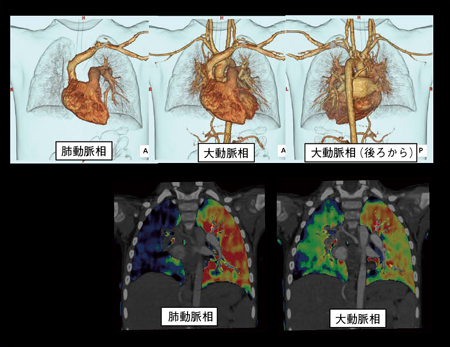

【背 景】撮影時2歳11か月の男児。身長93.5cm,体重12.5kg。既往歴に卵円孔開存(1か月時に自然閉鎖)。出生体重2550g,双胎第一子。繰り返す喀血を主訴に当院受診。単純X線,CT,核医学,カテーテル検査を施行し,右肺動脈欠損症と診断。今回のような症例の場合,右の肺動脈が欠損していても側副血行路がまわって,そこから血流がいっている可能性がある。肺動脈相と大動脈相がオーバーラップしてしまうと,どちらから血流支配を受けているのか判断が難しいため,今回は肺動脈と大動脈を分離して,Dual Energyの2相撮影を施行した。

【所 見】右肺動脈は認められず,気管支動脈や下横隔膜動脈,甲状頸動脈の分枝と思われる動脈の拡張が認められる。肺動脈相ではLung PBVにおいて右肺の血流が低下しているものの,大動脈相では側副血行路からの血流により右肺の血流が保たれていることが確認できる。今回,Dual Energy 2相撮影を行うことで解剖学的所見,肺血流分布,肺血流動態を把握することができている。

【ポイント】(1)医師の診断能力(CTにて血流分布を得ることができると確信し,2相の分離撮影を提案),(2)CT室のスタッフの経験(意思疎通のとれない2歳児に対し,テストボーラスを用いて造影タイミングを把握し,それに合わせスキャンスピードをコントロールして2相の分離撮影を確実に実施),(3)SOMATOM Definition Flashの性能(精度の良いDual Energy Systemと,小児の速い血流にも対応可能な装置のスペック)